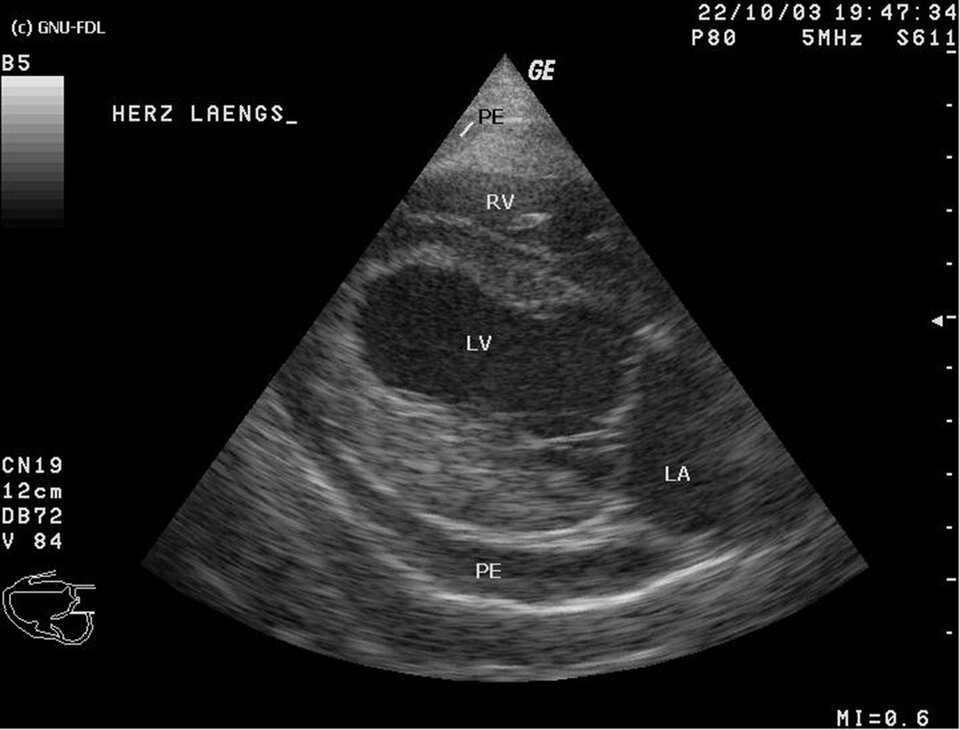

Serce to narząd wielkości zaciśniętej pięści i wadze ok. 0,5 kg, położony w klatce piersiowej po jej lewej stronie. Pełni on funkcję pompy – rytmicznie się kurczy i dzięki temu tłoczy krew do tętnic rozprowadzających ją po całym organizmie.

Serce otoczone jest podwójną błoną włóknisto‑surowiczą nazywaną osierdziem (workiem osierdziowym). Warstwa zewnętrzna osierdzia jest stosunkowo gruba i nieelastyczna, natomiast warstwa wewnętrzna - cienka i rozciągliwa i podzielona na dwie blaszki: ścienną i trzewną (nasierdzie). Pomiędzy nimi znajduje się wolna przestrzeń, nazywana jamą osierdzia, która wypełniona jest płynem surowiczym, zmniejszającym tarcie obu warstw podczas skurczów serca.

Serce podzielone jest na cztery jamy: dwa przedsionki (prawy i lewy) oraz dwie komory (prawą i lewą). Przedsionki oddziela od siebie przegroda międzyprzedsionkowa, a komory – przegroda międzykomorowa.